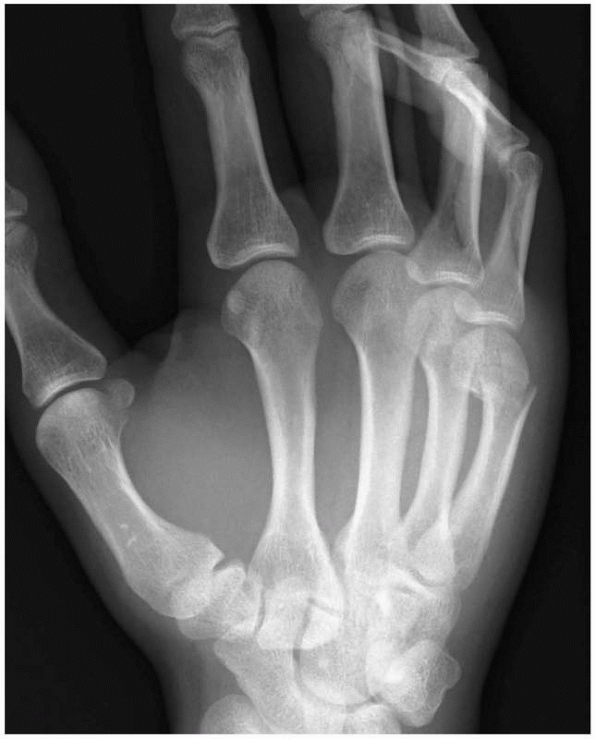

is used to treat metacarpal or phalangeal fractures. The wrist is

placed in 40 degrees of extension and the metacarpophalangeal joints

are placed in 70 to 90 degrees of flexion (Fig. 6-18).

The cast relies on the intact dorsal hood of the fingers acting as a

tension band or a soft tissue hinge. It is usually applied by placing a

slab over the dorsum of the forearm and the hand, with the wrist and

fingers in the correct position and then applying a forearm cast to

secure the slab. Finger extension is not permitted by the dorsal slab

but some flexion is allowed.

FIGURE 6-18 A Burkhalter cast. This is a combination of a forearm cast and a dorsal slab.